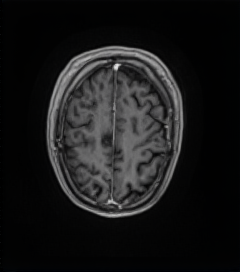

MRI